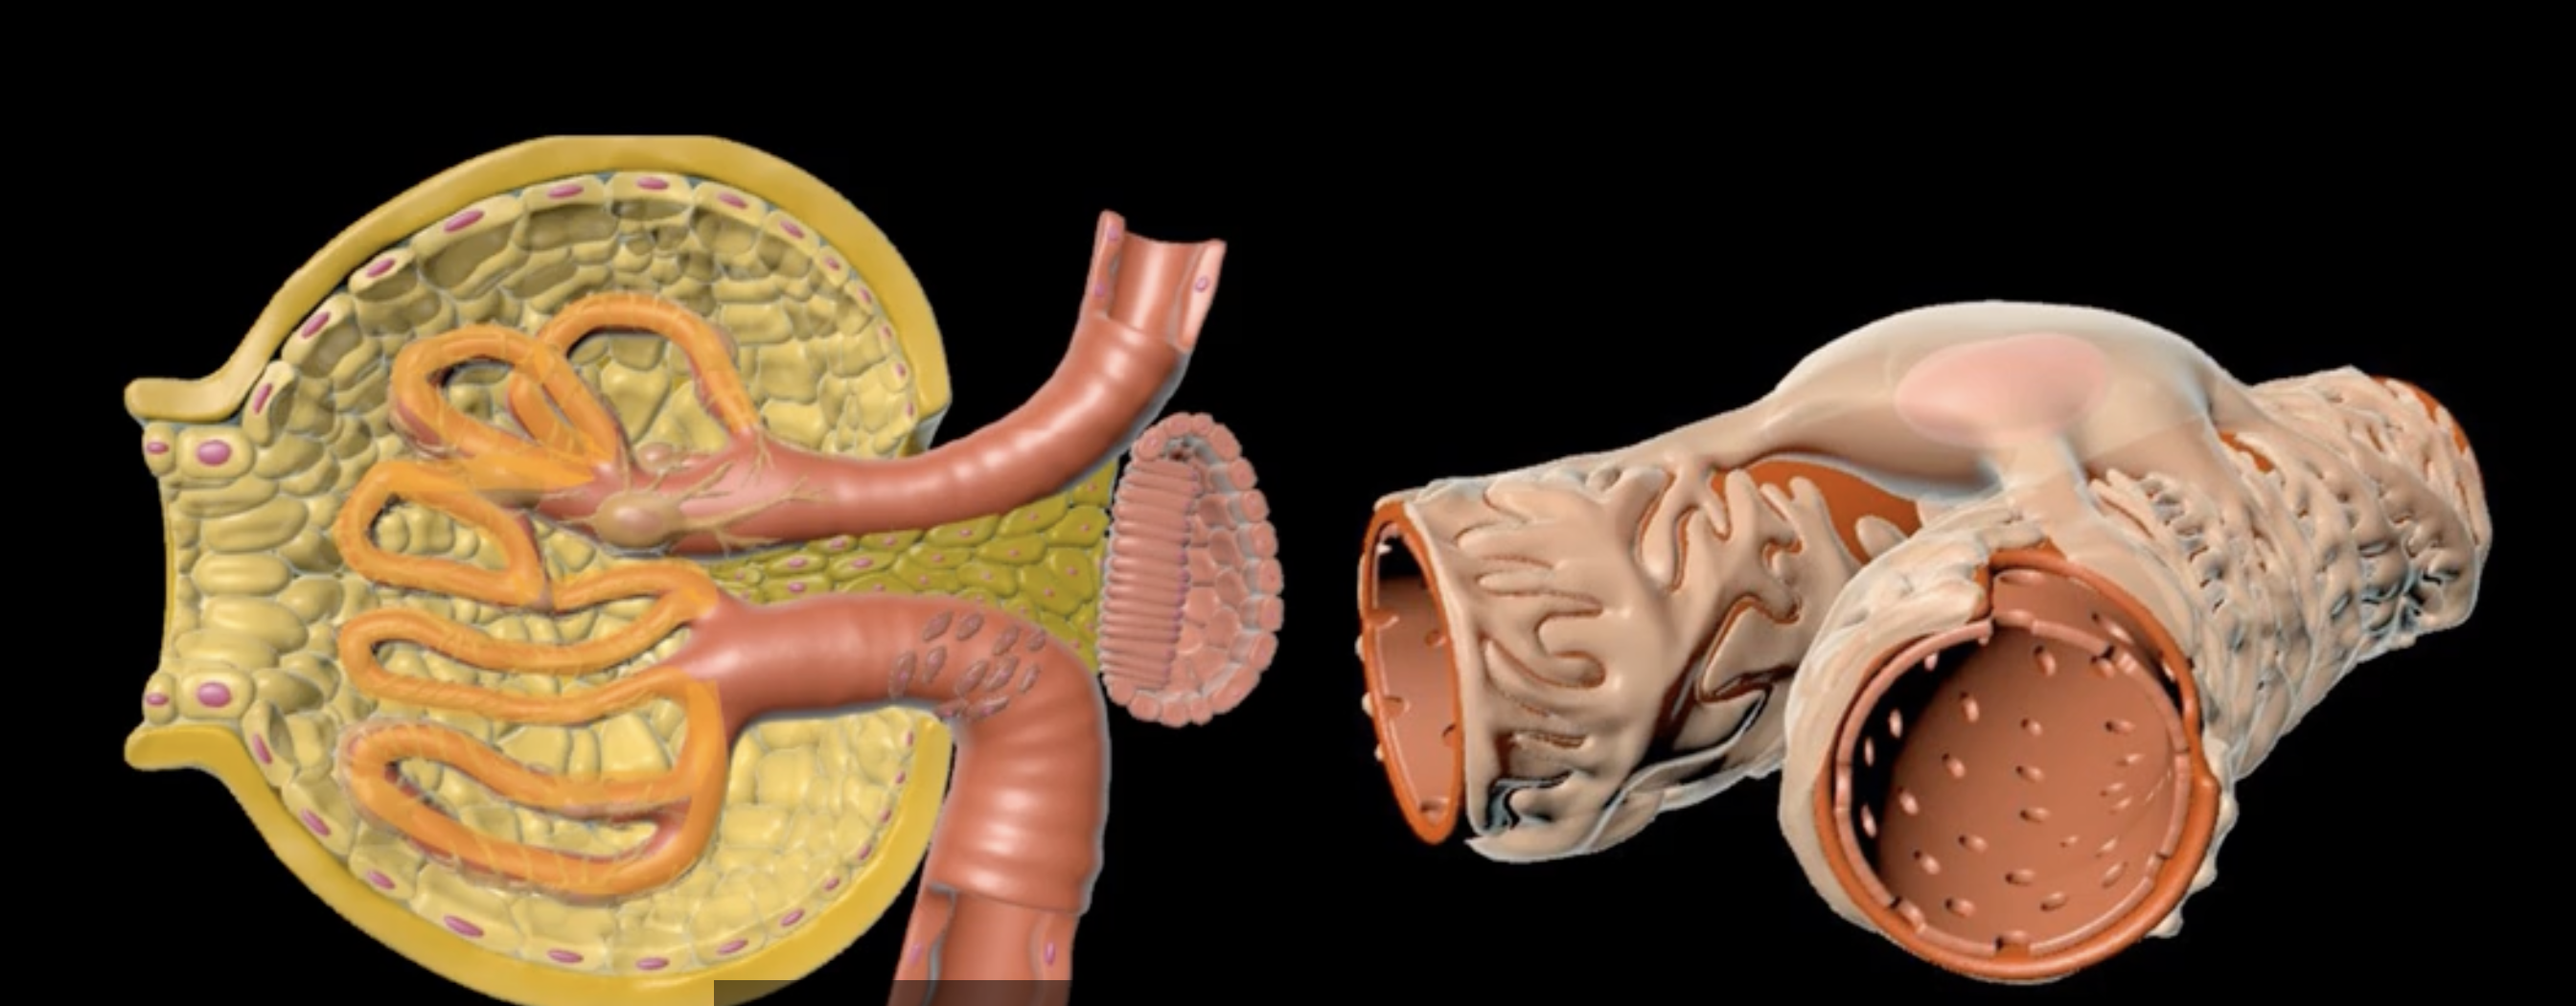

microvilli = purple

proximal convoluted tubule = green

right image: purple and green

yellow arrow= transcellular reabsorption

red= basolateral surface

light blue ring= apical surface

neon blue arrow = paracellular reabsorption

yellow arrow, red outer ring, light blue inner ring, and neon blue arrow

bowman’s capsule

orange

proximal convoluted tubule

green